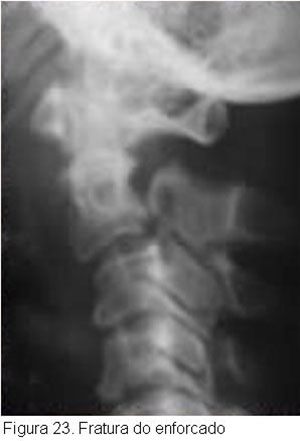

Diferentes mecanismos podem gerar esse padrão de fratura que erroneamente é considerado como fratura do enforcado de forma genérica para toda fratura pedicular de C2, isso se deve a similaridade radiológica dessas fraturas. Vale lembrar que esta equiparação classificatória é prejudicial para compreensão da magnitude das lesões associadas e planejamento de tratamento, visto que suas características clínicas e prognósticos são diferentes.

A anatomia não usual de C2 explica a particularidade desta fratura, pois o istmo alongado e fino de C2 acaba cedendo as forças traumáticas que são em geral melhor absorvidas pelo grande corpo de C2, potentes ligamentos posteriores e fortes músculos aderidos ao processo espinhoso largo e bífido. Entretanto a fratura pode apresentar desde mecanismo de extensão-distração, como no enforcamento judicial, esta clássica descrição de 1866 de Haughton sobre o padrão de lesão gerado pelo nó submentoniano foi corroborado pelo estudo de Wood-Jones, que sugeriu este posicionamento como o mais capaz de ser fatal dentre as diferentes posições em que o nó poderia se apresentar. Outros mecanismos mais freqüentes são: compressão axial, distrações e flexão, conforme observado em acidentes automotivos.

Essa fratura, apesar do grande escorregamento de C2 sobre C3 que freqüentemente aparece, muito raramente condiciona lesão medular, porque ela, ao contrário de produzir um estreitamento do canal espinhal, leva a um alargamento do mesmo. (Figura 23).